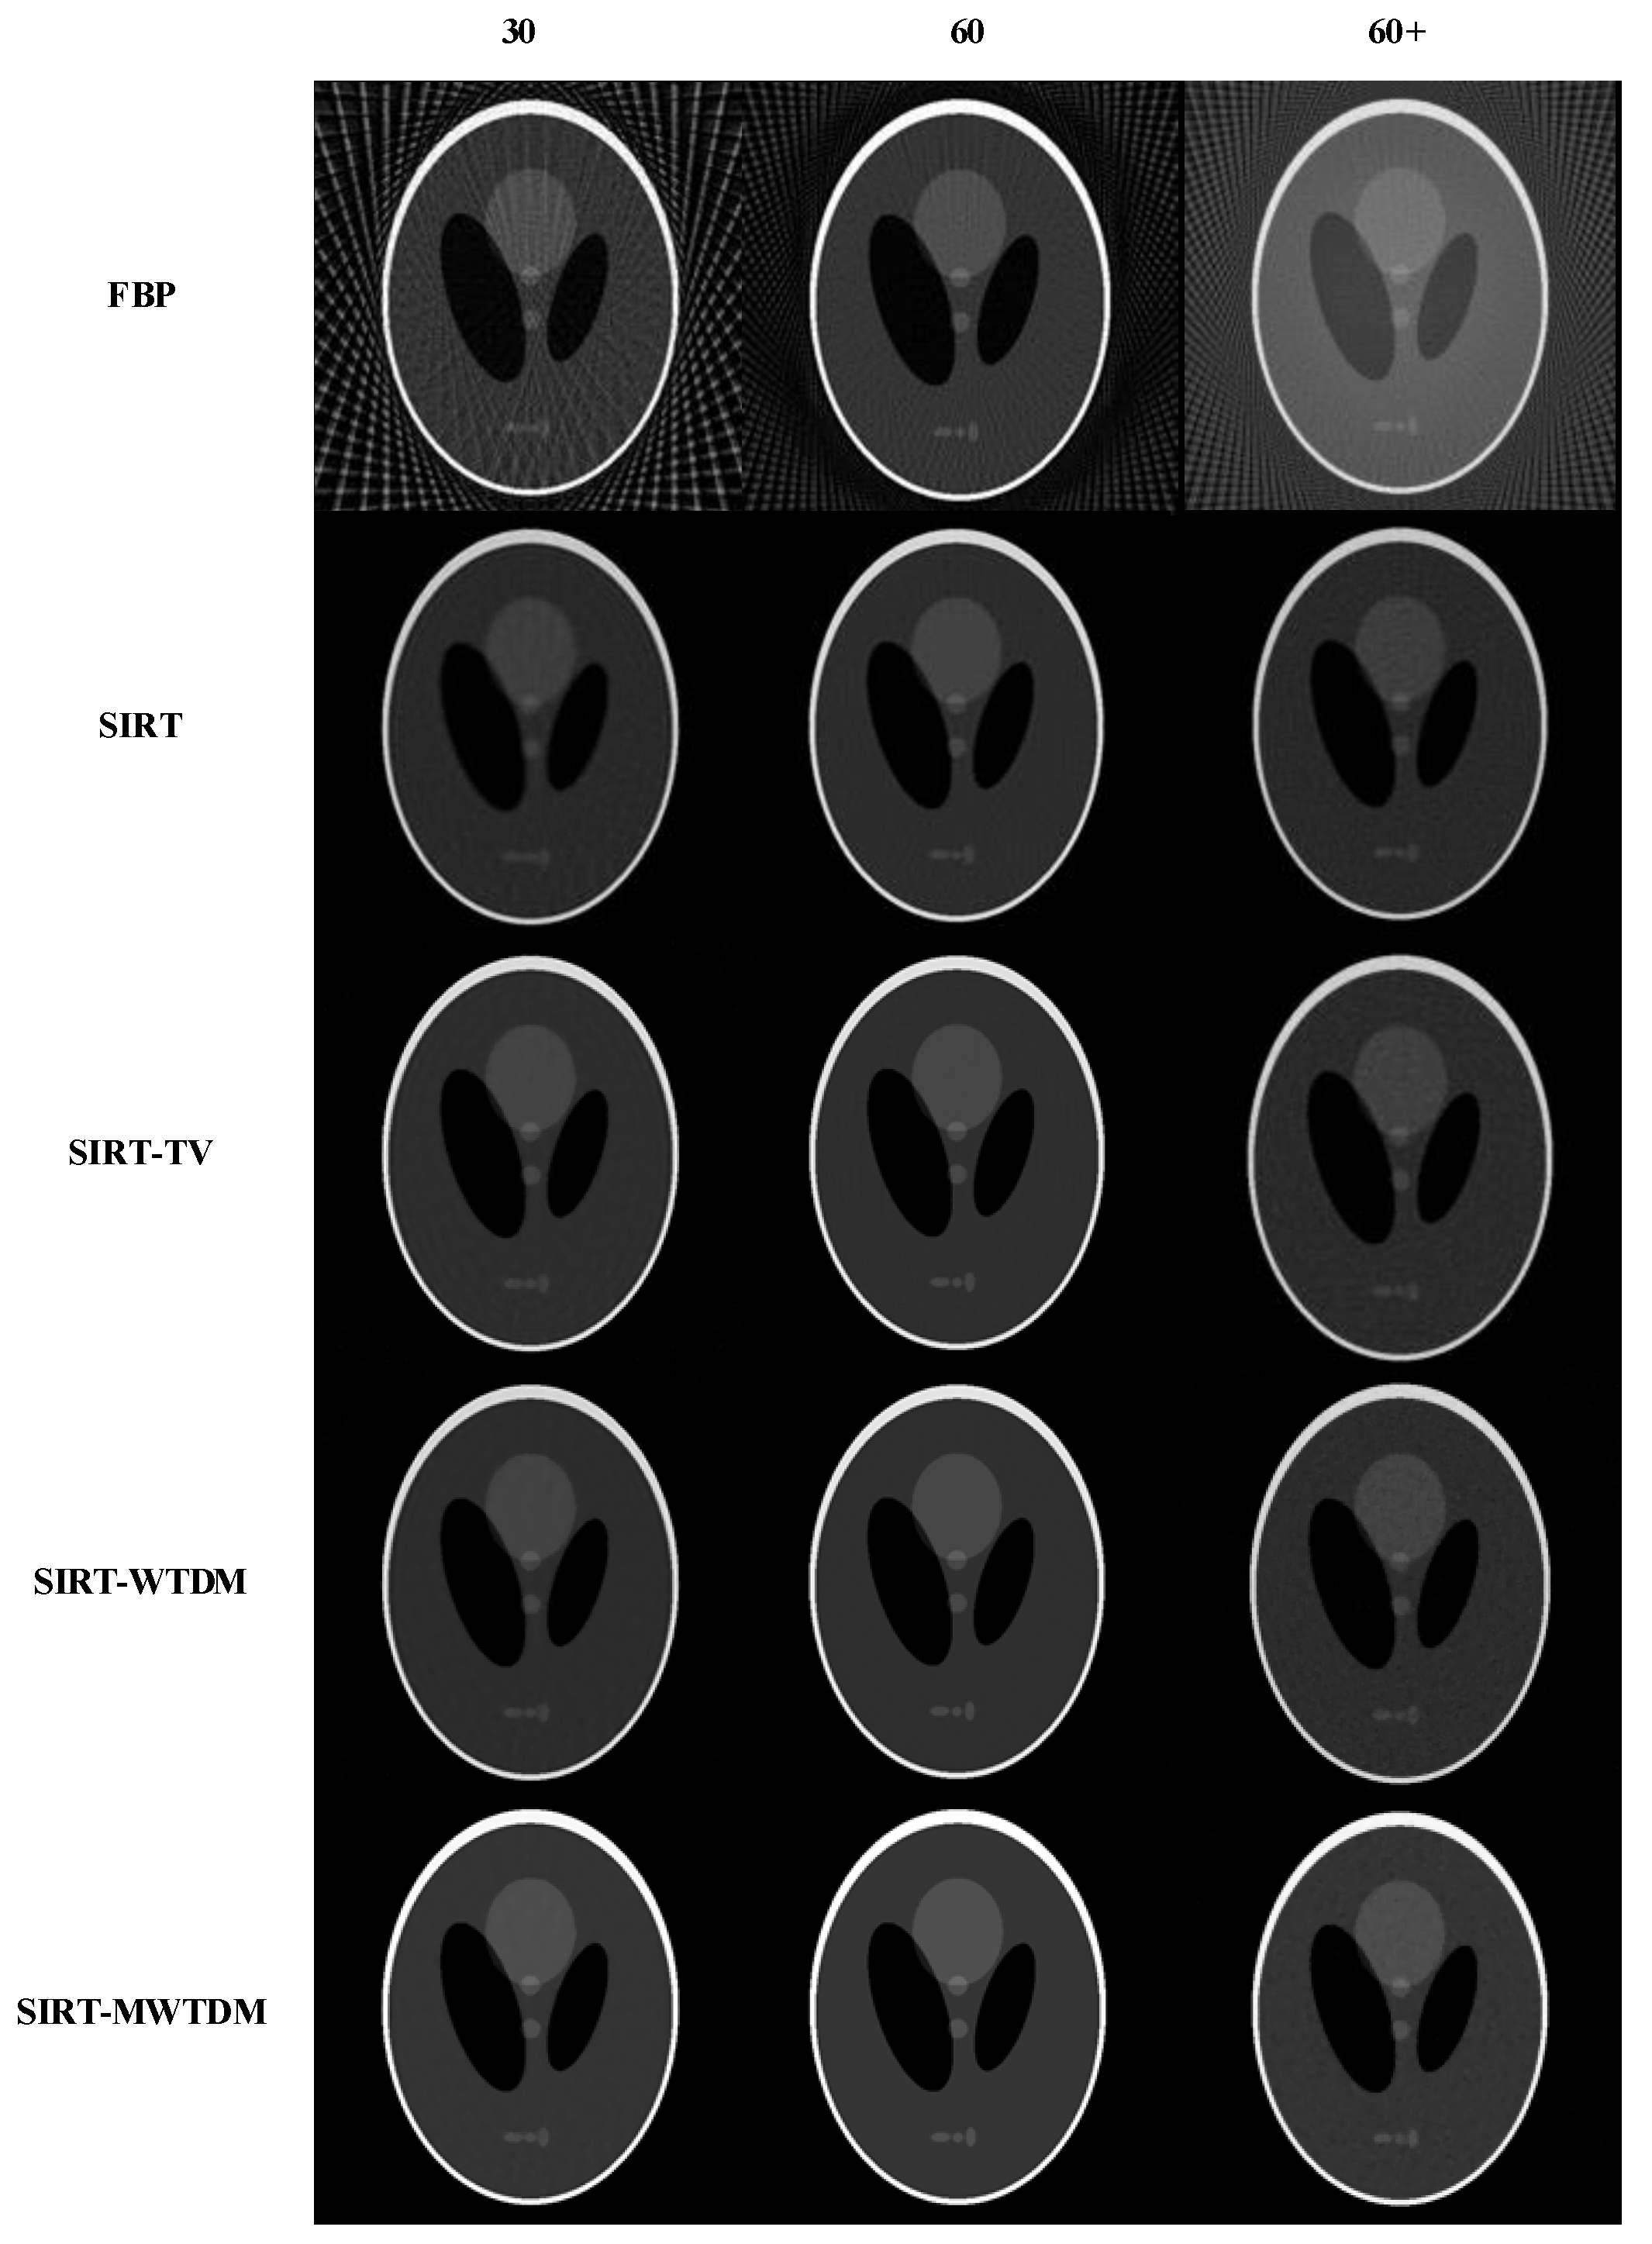

3.2.1. Shepp–Logan Phantom

3.2.2. Circular Phantom